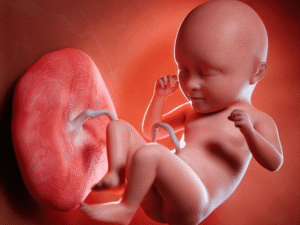

Nhau thai bám mặt trước là gì? Có nguy hiểm không?

Nhau thai bám mặt trước là tình trạng bánh nhau phát triển và bám vào ...

Vị trí nhau thai bám mặt trước hay mặt sau tốt hơn?

Khi mang thai, nhiều mẹ bầu quan tâm đến vị trí nhau thai, bởi đây ...

Nhau thai bám mặt trước có sao không? Cần lưu ý gì?

Nhiều mẹ bầu khi siêu âm thai kỳ thường nghe nhắc tới nhau thai bám ...